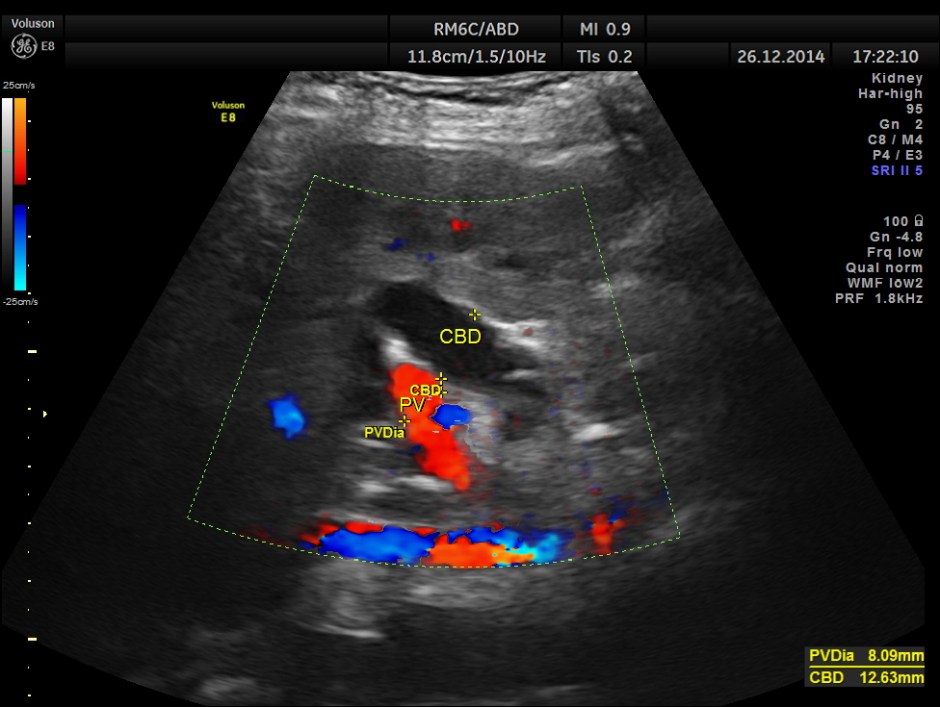

This was a 82 year old lady being evaluated for abdominal pain . Her serum bilirubin was very high and she was referred for an ultrasound .

grossly dilated common bile duct.